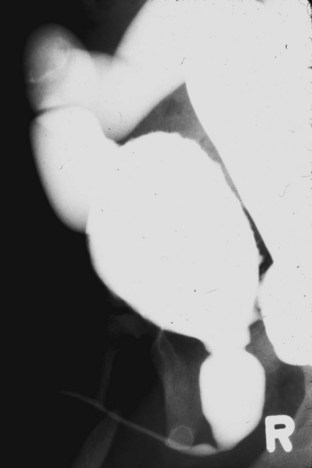

Anterior urethral obstruction is rare compared with posterior urethral valves. Although these obstructive structures may be called valves, they often occur in the form of a diverticulum of the urethra with one wall acting as an obstructive “valve” (Fig. 126–13) (Tank, 1987). There are also some reported cases of urethral flaps or valves in the anterior urethra (DeCastro et al, 1987; Scherz et al, 1987). The first case was reported in 1906, and the total number in the literature is small (Watts, 1906; Williams and Retik, 1969; Firlit et al, 1978).

Figure 126–13 A, Voiding cystourethrogram shows a severe case of anterior urethral valves. The bladder is almost empty, and there is massive reflux. The valve is in the form of a diverticulum. B, The filled diverticulum can sometimes be seen as a mass on the penis that resolves between voids. Pressing on the mass may express urine for some time after voiding.

Anterior urethral diverticuli typically occur where there is a defect of the corpus spongiosum, leaving a thin-walled urethra (Fig. 126–14). This segment of urethra balloons during voiding and causes a mass that is sometimes visible along the ventral wall of the penis. The mass resolves as urine drains from it between voids, and when full, urine can be expressed from the diverticulum by applying pressure. The distal edge of the diverticulum forms a flap that obstructs the flow of urine, and the effects of anterior urethral valves can be as damaging to the urinary tract as those of the posterior urethra. The embryology of these structures remains unclear but seems to be unrelated to the development of posterior urethral valves.

Figure 126–14 Voiding cystourethrogram demonstrates an anterior urethral diverticulum trapping urine during voiding.